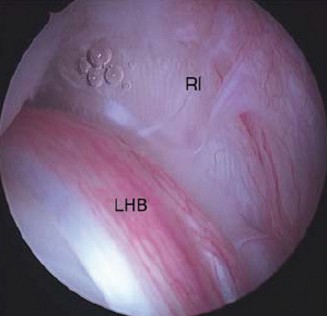

The correct answer is (C). This structure is a thickening of the coracohumeral ligament that starts anteriorly just posterior to the short head of the biceps tendon on the coracoid process, extends posteriorly through the edge of the avascular zone of the supraspinatus and infraspinatus, and ends at the inferior edge of the infraspinatus. One proposed function of the cable is to act like a cable in a suspension bridge, helping to evenly distribute forces on the humeral head produced by the rotator cuff (see Fig. 2–6).

Figure 2–6_Illustration showing the rotator cable and rotator crescent. B, rotator crescent; C, rotator cable; BT, biceps tendon; I, infraspinatus; S, supraspinatus; TM, teres minor. (Redrawn from Burkhart SS, Lo IKY. Arthroscopic rotator cuff repair. _J Am Acad Orthop Surg. 2006;14(6):333–346.)

The rotator crescent (Answer A) is the thin tissue that exists lateral to the rotator cable medial to the attachment of the supraspinatus and infraspinatus. It is composed on the tendons of these two rotator cuff muscles (see Fig. 2–6).

The rotator interval (Answer B) is the area on the anterior shoulder bordered by the subscapularis inferiorly and the supraspinatus superiorly.